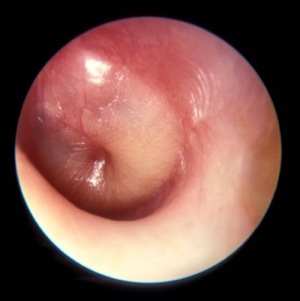

Otite media (vese a membrana timpánica inflamada) / commons.wikimedia.org |

Otite. A otite é unha enfermidade moi común, e é o que xeralmente coñecemos como a inflamación do oído. Esta acontece xeralmente na porción media do oído (otite media) como consecuencia da disfunción (mal funcionamento) da trompa de Eustaquio, que, contaminada por bacterias ou virus da cavidade nasal ou farínxea, producirá unha infección aguda.

Perda de audición. Consiste nunha perda da capacidade auditiva. Existen dous tipos principais de perda de audición. Un acontece cando hai unha lesión no oído interno ou no nervio auditivo e é permanente. O outro tipo acontece cando o son non pode chegar ao oído interno, o que se pode producir por acumulación de cera ou líquido, ou pola perforación do tímpano.